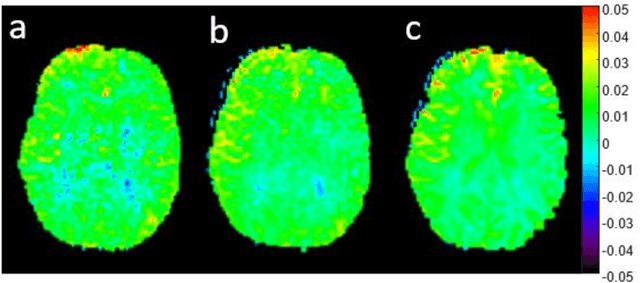

Abstract:Purpose: To substantially shorten the acquisition time required for quantitative 3D chemical exchange saturation transfer (CEST) and semisolid magnetization transfer (MT) imaging and allow for rapid chemical exchange parameter map reconstruction. Methods: Three-dimensional CEST and MT magnetic resonance fingerprinting (MRF) datasets of L-arginine phantoms, whole-brains, and calf muscles from healthy volunteers, cancer patients, and cardiac patients were acquired using 3T clinical scanners at 3 different sites, using 3 different scanner models and coils. A generative adversarial network supervised framework (GAN-CEST) was then designed and trained to learn the mapping from a reduced input data space to the quantitative exchange parameter space, while preserving perceptual and quantitative content. Results: The GAN-CEST 3D acquisition time was 42-52 seconds, 70% shorter than CEST-MRF. The quantitative reconstruction of the entire brain took 0.8 seconds. An excellent agreement was observed between the ground truth and GAN-based L-arginine concentration and pH values (Pearson's r > 0.97, NRMSE < 1.5%). GAN-CEST images from a brain-tumor subject yielded a semi-solid volume fraction and exchange rate NRMSE of 3.8$\pm$1.3% and 4.6$\pm$1.3%, respectively, and SSIM of 96.3$\pm$1.6% and 95.0$\pm$2.4%, respectively. The mapping of the calf-muscle exchange parameters in a cardiac patient, yielded NRMSE < 7% and SSIM > 94% for the semi-solid exchange parameters. In regions with large susceptibility artifacts, GAN-CEST has demonstrated improved performance and reduced noise compared to MRF. Conclusion: GAN-CEST can substantially reduce the acquisition time for quantitative semisolid MT/CEST mapping, while retaining performance even when facing pathologies and scanner models that were not available during training.